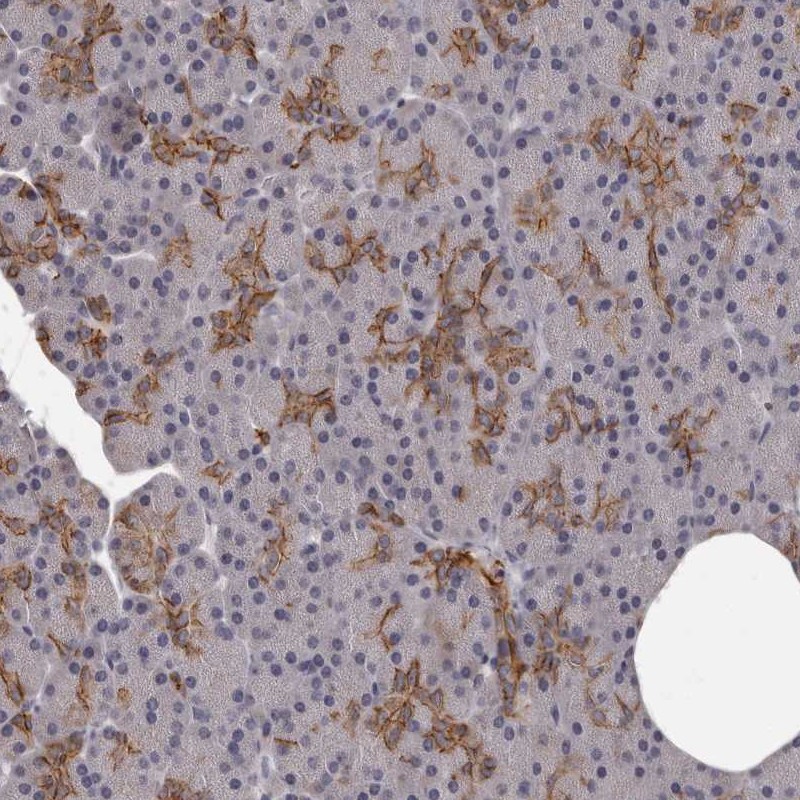

Immunohistochemical staining of human pancreas shows distinct cytoplasmic and membranous positivity in intercalated ducts.